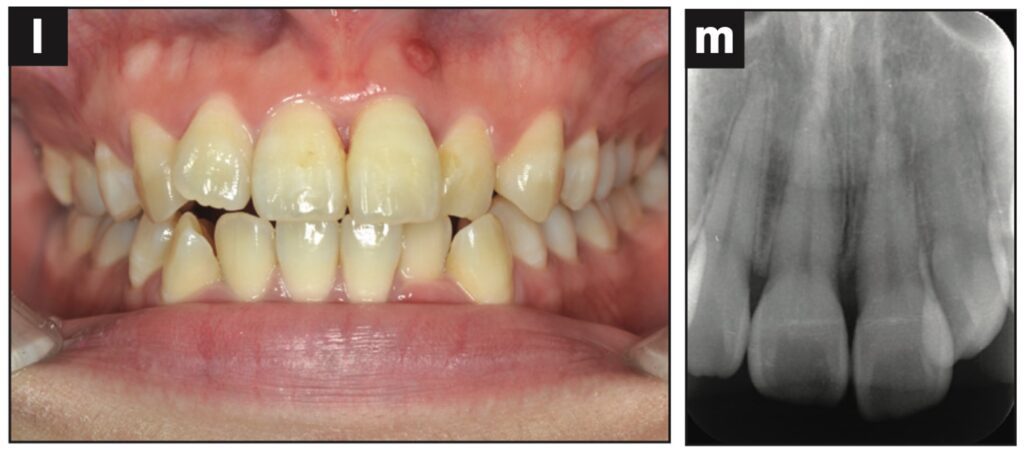

Bệnh nhân nữ 24 tuổi bị ngã khiến răng cửa giữa hàm trên bên trái bị lệch sang một bên. Sáng hôm sau, bệnh nhân đến phòng khám, được cố định bằng composite quang trùng hợp và lấy dấu.

Sáu tiếng sau, bệnh nhân quay lại và nhận hàm duy trì.

Bệnh nhân được hướng dẫn đeo hàm duy trì cả ngày trừ khi đánh răng. Các thử nghiệm độ sống tủy được thực hiện sau 1, 7, 14 và 21 ngày. Kiểm tra độ lung lay răng, gõ, sờ, thử tủy EPT và chụp X quang sau 28 ngày. Răng có độ lung lay +1 theo chiều ngoài trong và không có đáp ứng với thử nghiệm tủy EPT.

Ba tháng sau, răng đã được trám phục hồi và đáp ứng EPT (8/10). Tại thời điểm tái khám sau 4 tháng, răng đáp ứng với EPT (4/10). Sau 5 tháng, ghi nhận có lỗ dò. Răng không đáp ứng với EPT. Tổn thương quanh chóp được nhìn thấy trên X quang.

Răng được chẩn đoán là hoại tử tủy và điều trị tủy được thực hiện trong 2 lần hẹn. Một tháng sau (6 tháng sau khi chấn thương xảy ra), lỗ dò biến mất và chụp X quang cho thấy quá trình lành thương (hình 2).